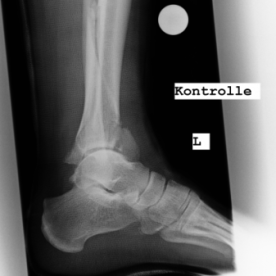

Röntgenbilder